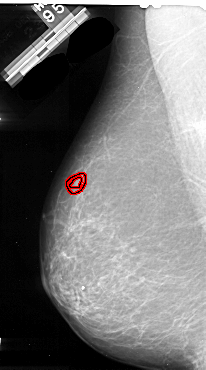

A_1094_1.LEFT_CC

LEFT_CC LINES 5251 PIXELS_PER_LINE 3061 BITS_PER_PIXEL 16 RESOLUTION 42 OVERLAY

FILE: A_1094_1.LEFT_CC.OVERLAY

TOTAL_ABNORMALITIES 1

ABNORMALITY 1

LESION_TYPE MASS SHAPE IRREGULAR MARGINS ILL_DEFINED

ASSESSMENT 4

SUBTLETY 2

PATHOLOGY MALIGNANT

TOTAL_OUTLINES 1

BOUNDARY